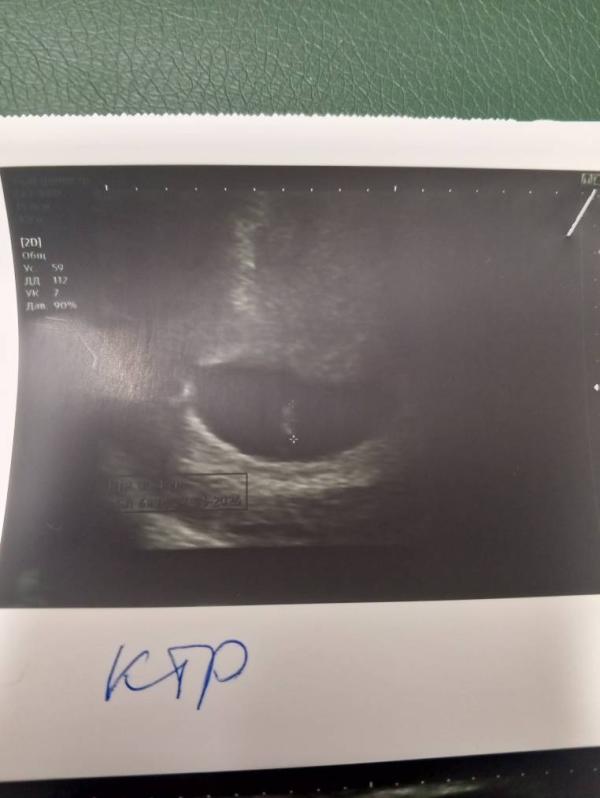

Отставание по КТР на сроке 6.4 недели: что делать

Моё зёрнышко . По ктр срок 6.4 сегодня , отстаем, надеюсь ещё догонит 🙏 а если нет ничего страшного 😊